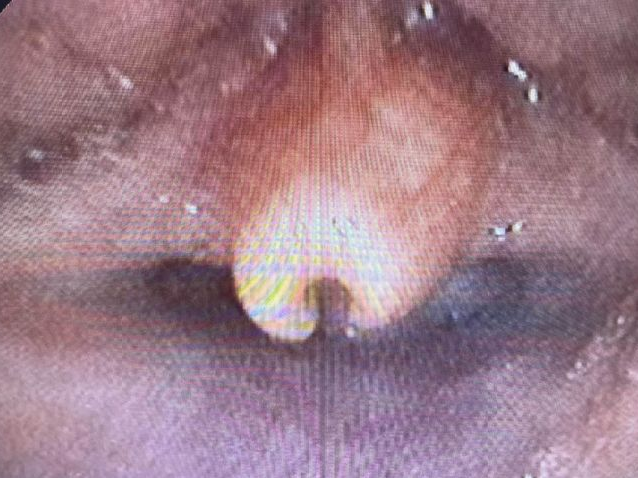

岳阳市中医医院儿科主任雷东方接诊患儿时,根据家长的描述,认真细致地听诊、体查后,认为宝宝发出的“呼噜呼噜”的声音,可能是喉软骨软化症。随后排纤支镜检查。果不其然,患儿镜下会厌软骨明显软化、卷曲、倒伏,证实了这一诊断。

↑↑↑正常(左)与喉软化症(右)对比图↑↑↑